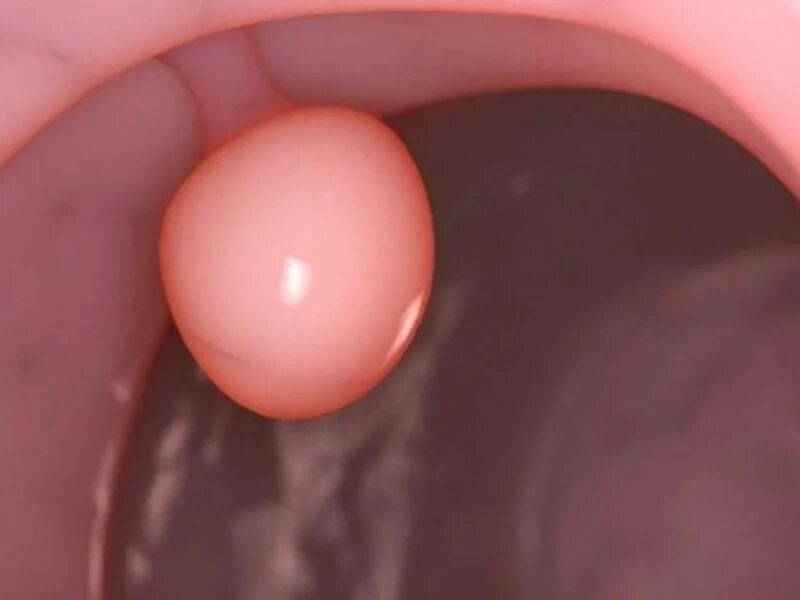

Полип эндометрия матки без операции